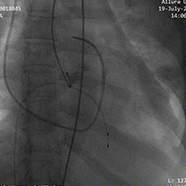

1.根据术前测量分析,采取右侧股动脉作为主入路,左股为辅入路。置入猪尾进行根部造影,造影可见主动脉根部大量钙化,瓣叶活动度低,冠脉支架灌注良好,无明显反流。

根部造影

2.18mm球囊预扩,腰征明显,冠脉显影良好,无明显瓣周漏

18mm球囊预扩